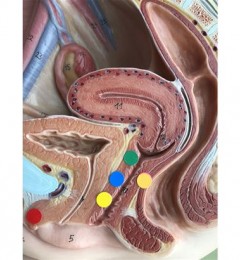

举个例子:孕妇在整个妊娠期约需1 000毫克铁(比非妊娠妇女增加15%—20%),其中胎儿需铁400~500毫克,胎盘需铁60—100毫克,子宫需铁40—50毫克,母体血红蛋白增多需铁400—500毫克,分娩失血需铁100~200毫克。所以建议还是以动物来源的血食补为主。尽管动物的肝脏含丰富的铁,但不建议孕期吃得太多,因为肝脏里面含过多的维生素A和胆固醇。